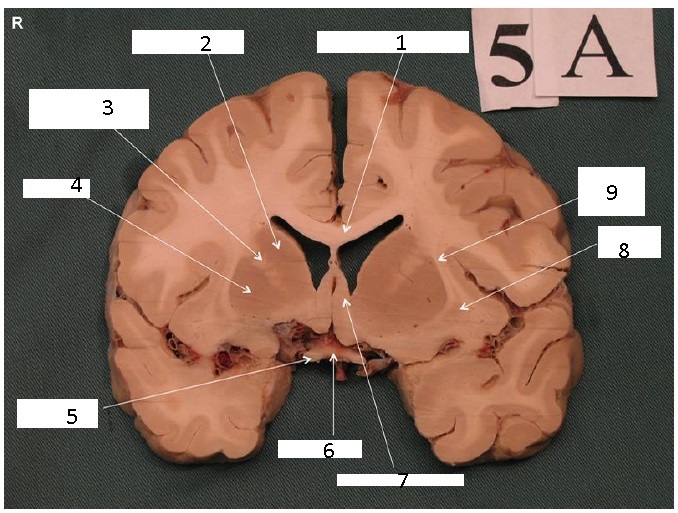

Identify 1

Body of Corpus Callosum

Identify 2

Head of Caudate Nucleus

Identify 3

Anterior Limb of the Internal Capsule

Identify 4

Putamen

Identify 5

Claustrum

Identify 6

Insula

Identify 7

Nucleus Accumbens

Identify 8

External Capsule

the lateral portion of the ‘A’ formed by the external and internal capsule

Identify 9

Cingulum

Identify 10

Cingulate Gyrus